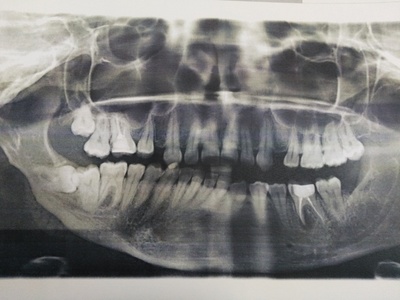

А для того, что ортопантомография (ОПТГ, обзорный или панорамный снимок зубов), является плоскостным, а значит происходит наложение каждой детали снимка послойно друг на друга. Следовательно, рассмотреть объект исследования, в частности, область зуба мудрости, расположенного рядом нижнечелюстного нерва, во всех плоскостях, под иным углом или другой проекции невозможно. КЛКТ (Конусно-лучевая компьютерная томография), напротив дает нам такую возможность.